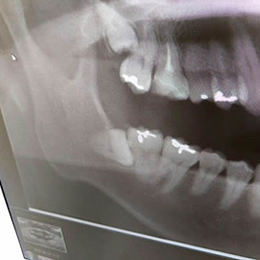

智歯(親知らず)

智歯の位置はさまざまで、形や根の方向や曲がり具合など、3次元でなければ把握できない情報が多くあります。

神経の走行を正確に知ることもできるので、開業医で抜歯ができるかどうかも含め、安全性が高まりました。